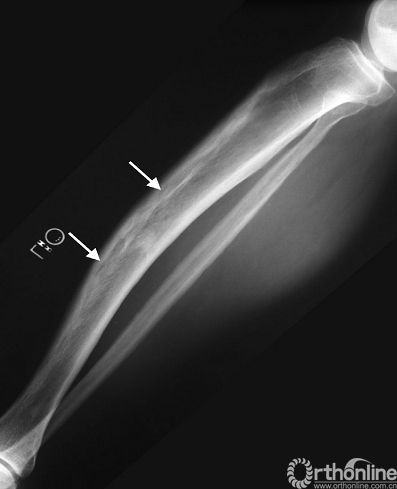

影像学特点:佩吉特病有典型的X线表现,粗大的骨小梁,增厚的骨皮质及病变骨直径的增大(图11)。疾病的进展典型的表现为先溶骨性改变后发展为成骨性改变,但大部分是混杂在一起同时进行的。在脊柱侧位片上,椎体四面的骨皮质增厚形成“相框”样外观改变。负重的下肢骨骼,特别是胫骨,在长期病变过程中可能导致弯曲畸形(图12)。

图12. 佩吉特病致胫骨弯曲畸形,长期病变使长骨弯曲变形,也可见皮质增厚和“火焰样”的皮质骨溶解(箭头)。